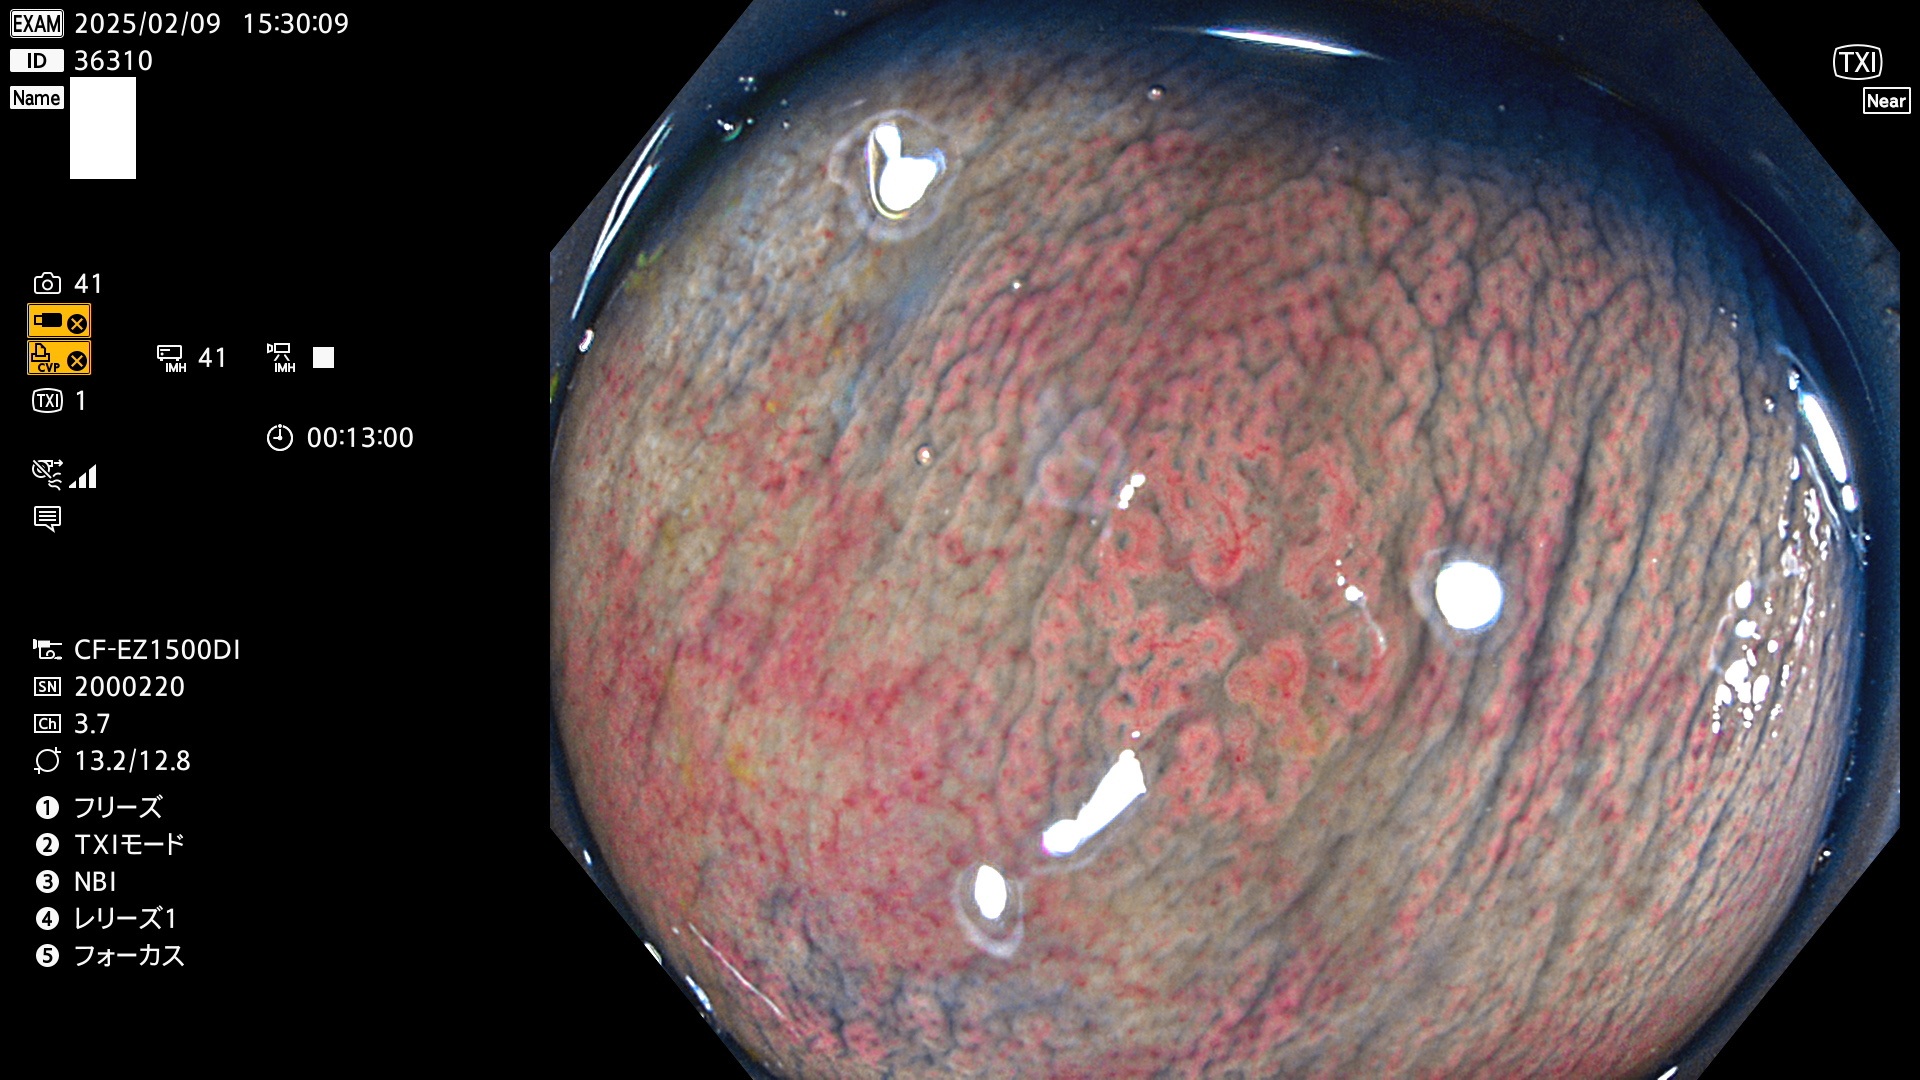

今週のUb、Uc型腺腫

完全に平坦な物をUb、陥凹している物をUcと呼びます。最も発見が難しく危険な病変です。

毎週の検査(木・金・土・日)に発見されたUb、Uc型・腺腫を、その週の日曜の夜にUPし1週間、提示します。

抽出の対象期間 2025年2月6日〜2月9日の4日間(48件の検査)7個 (7/48=14%)